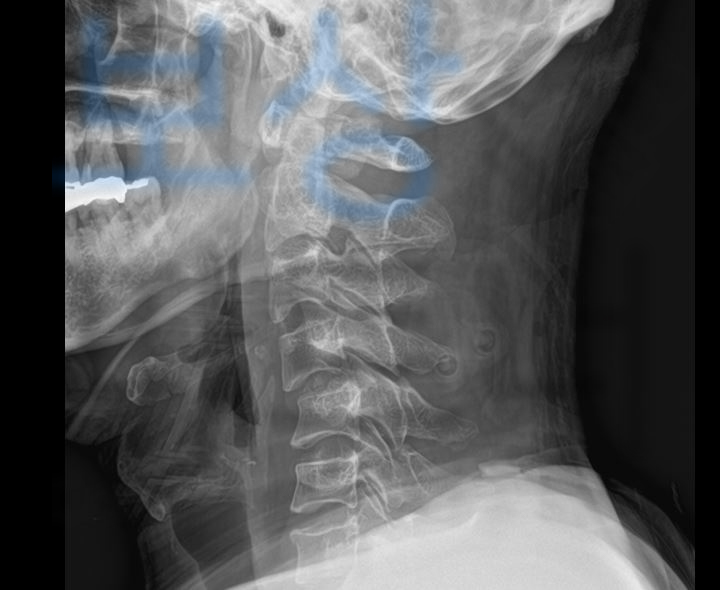

오늘은 C4번 C5번 경추 탈구 및 C7번 경추 골절 수술하신 의뢰인 김@@님의 산재와 근재 보상사례 소개해드리도록 하겠습니다.

보상파트너로 연락주신 의뢰인은 무거운 유리 적재물이 떨어지면서 머리를 가격당하는 사고를 당하셨습니다. 의뢰인은 사고 이후 머리, 어깨, 목 등 복합 부위 통증을 호소하셨고 병원 응급실 내원하여 정밀 검사를 받으셨습니다.

그 결과 의뢰인은

경추4번 ~ 5번 탈구 및 경추7번 골절 진단을 받으셨습니다. 의뢰인의 상태는 수술하지 않을 수 없는 심각한 상황이었기 때문에 경추 골절 수술을 진행하게 되었고

경추 4번과 5번 척추체를 고정하는 즉** < 경추 전방 유합술 >** 을 진행하게 되었죠.